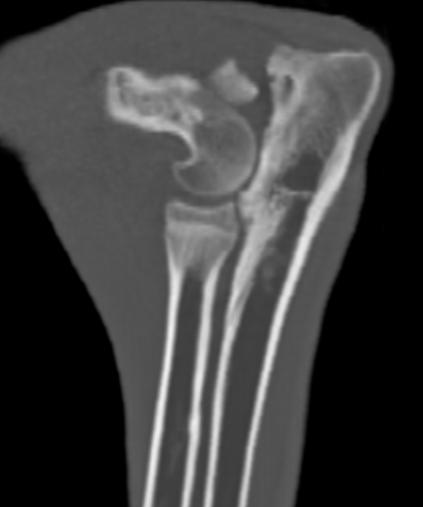

kV, 28 mA, radius ­ 48 kV, 28 mA, femur ­ 52 kV, 28 mA și tibie ­ 48 kV, 28 mA.

Computer tomografia a fost realizată cu aparatul Somatom Definition AS64 Slice (mod de scanare în spirală) – Siemens GmbH, împreună cu aplicația software pentru procesarea imaginilor Syngo CT 2011A – figura 3.

La patru dintre cazurile remediate prin MIPO, la momentul vindecării osoase (certificată radiografic) s­au extras materialele de osteosinteză și, din nou, calusul a fost evaluat pe imagini de tip computer tomograf (figura 4), după metoda propusă de Wullschleger – 2010, respectiv: I. Numărul de punți de calus: ­ pe secțiunea transversal proximală s ­ au luat în considerare 4 regiuni (dorsală, ventrală, la ­

Figura 4. Evaluarea CT a scorului de vindecare secundară după MIPO a unei fracturi de femur (656/26.10.2012). A - secțiune transversală proximală – calus parțial mai gros decât coticala osului (săgeata albă). B - secțiune transversală distală – calus total mai gros decât corticala osului (săgeata albă) și calus total mai subțire decât corticala osului (săgeata neagră)

terală, medială) și s ­ a notat cu 1 punct prezența punților în regiunea respective); ­ pe secțiunea transversală distală s ­ a procedat în mod identic. Prin însumarea punctelor, s ­ a obținut un punctaj între 0 și 8. II. Dimensiunea punților de calus: ­ secțiunea transversală localizată proximal și distal de focarul de fractură, punctându ­ se separat: n fără calus – 0, n calus total mai subțire decât corticala osului – 1, n calus parțial mai gros decât corticala osului – 2, n calus total mai gros decât corticala osului – 3. Se însumează scorul obținut pentru fiecare secțiune. Maxim 6 puncte.

Dacă puntea de calus se întinde între cele două secțiuni, la scorul obținut se adaugă 1.

Scorul total se obține din înmulțirea valorilor obținute la cele două categorii și poate avea valoarea maximă de 56.